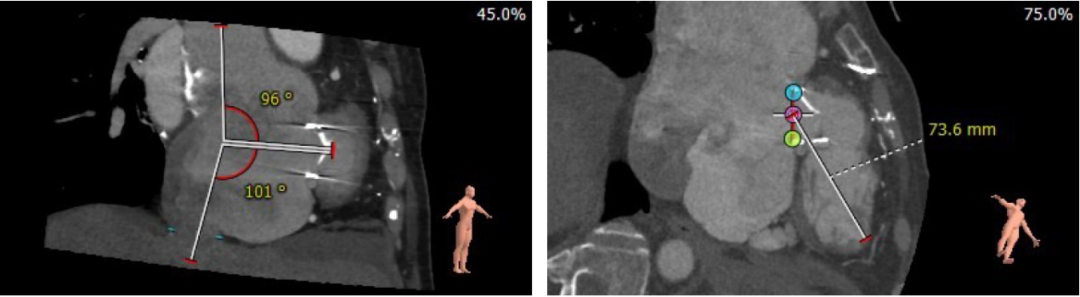

患者18年前外科手术置换的三尖瓣生物瓣为国产普惠牛心包29#瓣膜,术前CT结果显示,患者三尖瓣生物瓣梗阻,有两片瓣叶几乎不能活动,左右心房扩大,右室与右房几乎平行,且右室非常小。因此为保证手术安全,减少导丝在右室造成的风险,改用肺动脉路径置入支撑导丝换瓣。三尖瓣生物瓣瓣环面积为509.2mm2,平均内径为25.5mm,选用29mm爱德华SAPIEN 3 瓣膜并加1ml体积容量尽量扩张瓣膜至喇叭状,能最大程度减少术后压差,提高患者生存质量。

术前CT分析